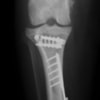

Fixin T字プレート使用して固定

・術後レントゲン

手術前TPA 28.4° が術後TPA 11.7° に矯正されました。

術前TPA計測

術後TPA計測

当院ではFixinmicroプレートを使用して小型犬のTPLO手術を実施しております。